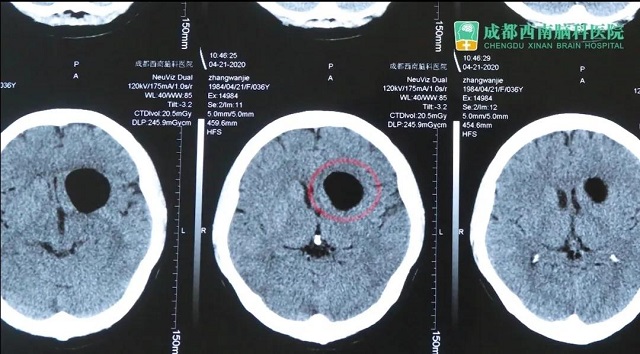

患者辗转多院后来到我院,经门诊医生进行流行病史调查无新型冠状病毒肺炎地区旅游集居住史,无新型冠状病毒肺炎密切接触史,无发热、乏力、咳嗽及腹泻症状,门诊血常规、CRP、 胸部cT检查,排除新冠状病毒肺炎,门诊以“左侧前颅底肿瘤”收入我科。之后在我院进行了肿瘤切除手术。

患者1月前于贵黔国际总医院,行头颅MRI示:鞍上占位,脑电图:异常脑电图(左侧颞中央区局灶性改变) 。医院建议手术治疗,遂就诊于贵州医科大学附属医院,行头颅CT:鞍上池区域占位,考虑畸胎瘤可能,建议转院手术治疗。